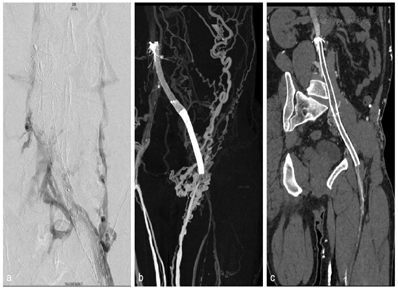

双下肢静脉CTV像示左侧髂外静脉-髂总静脉-下腔静脉支架留置影,左侧髂外静脉远端可见少许对比剂充盈,余支架管腔内可见低密度充盈缺损影,左侧髂外静脉、髂总静脉未见对比剂充盈;左侧腹股沟可见多发侧支血管显影,左侧腹壁内侧-左肾静脉侧支血管建立影像(图1,图2),右侧髂外静脉、髂总静脉及下腔静脉可见对比剂充盈,密度不均匀;双足、双下肢皮下多发迂曲静脉显影,双侧大隐静脉充盈良好,左侧股静脉近端充盈缺损,血管纤细,密度不均(图1)。诊断:左侧髂外静脉-髂总静脉-下腔静脉支架留置,支架内血栓形成,左侧腹股沟区、左侧腹壁内测-左肾静脉及腹壁静脉建立。介入治疗后复查双下肢静脉CTV,可见左侧大隐静脉开口以近支架内血管大致通畅,支架以远端下肢静脉未见明确显影,左侧腹股沟区侧支循环较前减少,左侧腹壁内侧-左肾静脉侧支血管较前减轻(图3、图4)。

下肢静脉栓塞的诊断金标准为DSA检查[1],但DSA是有创检查,准备时间长,耗费人力物力,同时DSA存在过量辐射暴露风险且检查费用较高,检查过程中易损伤血管壁导致新鲜血栓形成[2,3,4]。对比DSA,CT血管检查操作简便,显影效果好,安全微创,对比剂用量少,成像范围大,辐射剂量低。根据对比研究,可以准确评估下肢静脉的通畅性,能展现整个下肢静脉系统情况及静脉栓塞疗效评估,与DSA吻合度高。双源CT低kV高mAs球管技术,在降低患者辐射剂量前提下,增强了碘对比剂衰减,在CT血管检查中用低流速低对比剂用量亦可获得高质量的CT血管诊断图像。本例双下肢CTV采用90kV,双筒双流速度2.5ml/s直接注入下肢静脉各100ml混合剂(造影剂10%+盐水90%),可获得可观的静脉血管图像(图1)。对比常规CT(120kV),低kV技术大幅度降低辐射剂量。此外,CT血管后处理灵活方便,结合探针分析,更是可以细节、清晰地观察支架内外管腔及管壁情况(图2、图3),为临床诊断提供准确的影像学资料,为患者病变及时发现及进一步治疗提供可靠依据[5]。CT作为微创检查方式,"三低"双下肢CTV可常规应用,替代传统120kV,满足临床诊断需求同时提高患者的舒适度,降低辐射剂量,减少并发症,并适合血栓患者术前明确诊断及术后疗效评估(图4)。为了实现常规低kV血管成像,其他先进的技术也被使用,如CARE Dose4D(实时自动曝光控制)和ADMIRE(高级模型迭代重建)。在本病例中,有效剂量仅为0.65mSv。